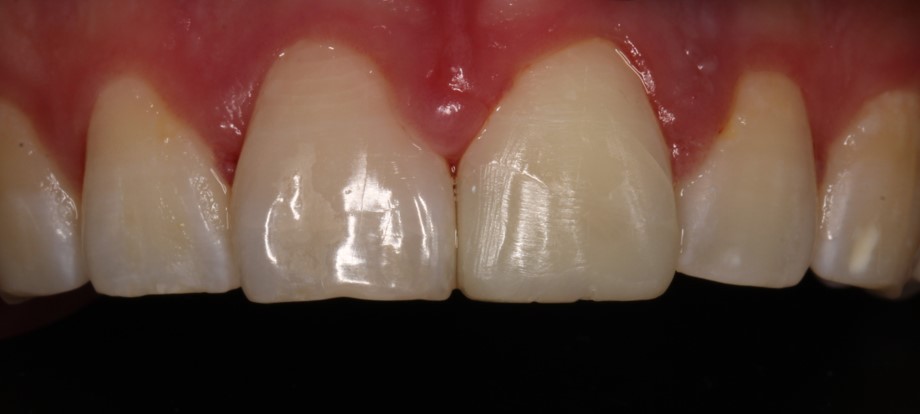

Наблюдение: Фотографии спустя 1 год и 8 месяцев. 22.06.2024г.

Была проведена незначительная корректировка и отполировали до блеска

Фотография с поляризационным фильтром